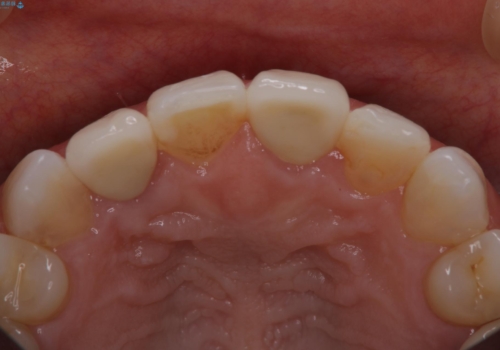

歯茎の出来もながなくなり、患者様にセラミックの色も満足いただけました。